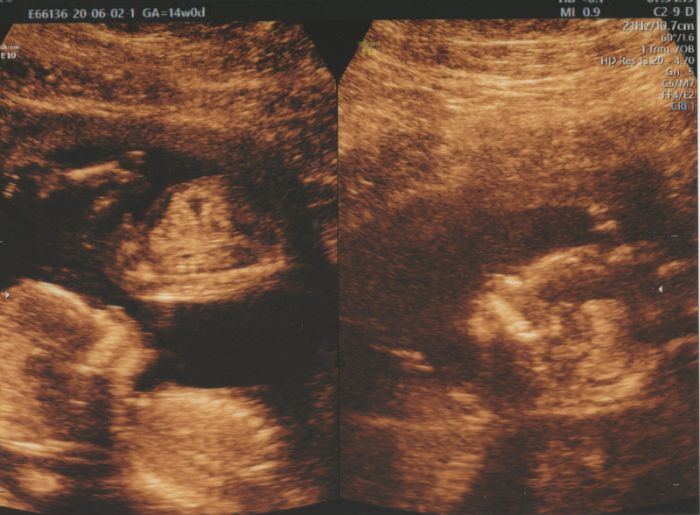

Ahoj holky , dlouho jsem tu nebyla..... Screening jsem mela cca před 3 týdny. Vse v pořádku

a s největší pravděpodobností to bude chlapeček

Ahoj holky,dnes screening 13+5,miminko je zdrave

Pan doktor mi rekl,ze si mam pohlavi zjistit sama,ze ho nikomu nerika.Zajel mezi nozky a rika"Tady ma jedno,tady ma druhy a neni to pupecnik".Takze asi cekame chlapecka?

Tak už i my jsme konečně po screeningu. Morfologicky všechno vypadalo dobře, výsledky genetiky budou večer. Nakonec je všechno trochu jinak, než jsme čekali - prcci mají společnou placentu, takže jsou to jednovaječná mo-bi dvojčátka. Bohužel je tím všechno komplikovanější, nezbývá než doufat, že placenta vydrží až do 36. týdne, kdy je nejzazší termín porodu. Moc jsem se těšila na holčičku, když už doma jednoho kluka máme, ale vypadá to na čistě mužskou smečku :)